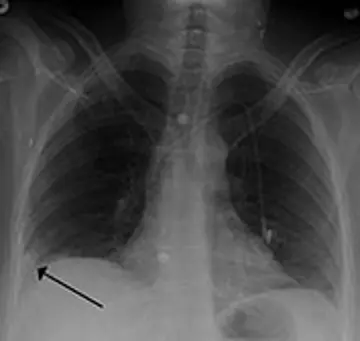

تشخیـص آمبولی ریه